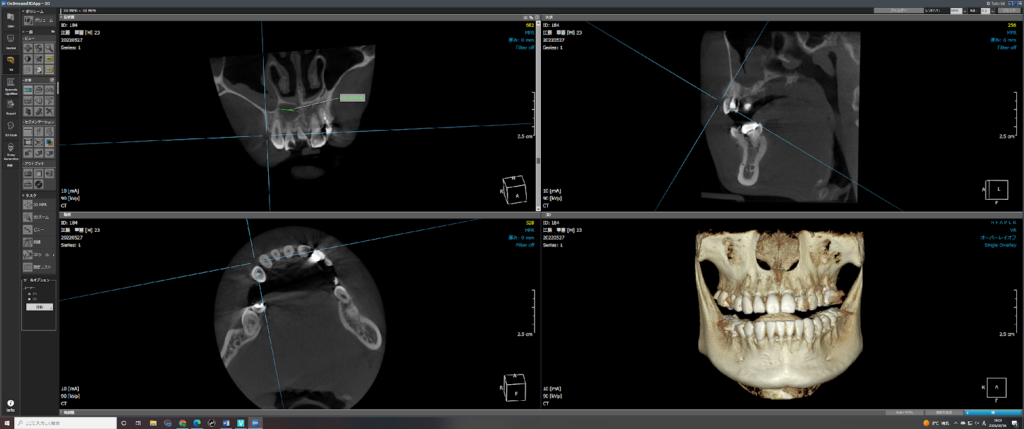

レントゲン・CTによる精密検査

X線写真では、歯の根の先に黒く抜けた影として嚢胞が確認できます。ただし大きさや位置によっては分かりづらい場合もあります。

三次元画像が得られる歯科用CTでは、嚢胞の位置や

骨への影響などをより正確に把握することができます。

手術が必要なケースでは特に重要です。